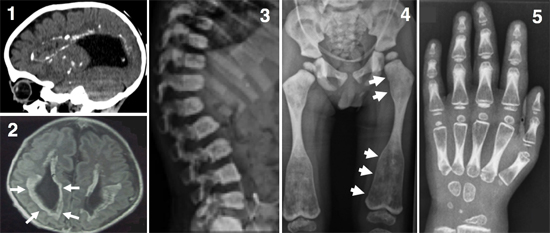

図1 骨と脳を侵す新たなタイプの難病の表現型

- 1: 脳のCT像(側面像)。脳室の拡大(脳内黒い部分)と脳内の多数の石灰化(白い部分)が見られる。

- 2: 脳のMRI像(冠状断)。脳の萎縮、脳室周囲の神経変性を示す高信号領域(白矢印)が見られる。

- 3: 脊椎椎体のX線像。椎体の扁平化と硬化が見られる。

- 4: 骨盤・下肢のX線像。骨の濃度の増加が見られ、大腿骨骨幹端部の拡大(白矢印)が特徴的である。

- 5: 手の骨のX線像。骨の濃度の増加が見られる。

研究チームは、最近収集した難病患者の中に、共通の骨格、脳神経系の異常を持つ3家系7人の患者を発見しました。骨格には、全身の骨硬化(骨の濃度の上昇)、脊椎の形成異常、長管骨と短管骨の骨幹端部の拡大などの特徴的な異常が、脳には、脳室(脳内部にある脳脊髄液で満たされている空間)周囲の石灰化を伴う白質脳症[9]様の神経変性とダンディ・ウォーカー奇形[10]などの脳奇形が認められました(図1)。このような骨格、脳神経系の異常の組み合わせは過去に報告がなく、新たな症候群であると考えられました。そこで、研究チームはその原因遺伝子の同定を試みました。